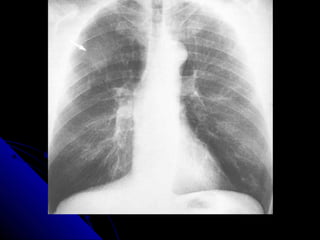

NNoodduullee//mmaassss

NNoodduulleess aanndd mmaasssseess iinn tthhee lluunngg aappppeeaarr aass

rroouunndd wwhhiittee lleessiioonnss.. IIff tthhee lleessiioonn mmeeaassuurreess lleessss

tthhaann 33 ccmm,, iitt iiss ccaalllleedd aa nnoodduullee.. IIff iitt iiss llaarrggeerr tthhaann

33 ccmm,, iitt iiss ccaalllleedd aa mmaassss..

AA nnoodduullee//mmaassss iiss ccaauusseedd bbyy eeiitthheerr aa mmaalliiggnnaanntt

((ee..gg.. lluunngg ccaanncceerr,, mmeettaassttaassiiss)) oorr bbeenniiggnn pprroocceessss

((ee..gg.. hhaammaarrttoommaa,, ggrraannuulloommaa))..

PPrriimmaarryy lluunngg ccaanncceerrss tteenndd ttoo hhaavvee iillll--ddeeffiinneedd,,

ssppiiccuullaatteedd bboorrddeerrss.. MMeettaassttaasseess tteenndd ttoo pprroodduuccee

mmuullttiippllee ssmmooootthh rroouunndd lluunngg nnoodduulleess,, oofftteenn ooff

vvaarriiaabbllee ssiizzee.. BBeenniiggnn lleessiioonnss tteenndd ttoo bbee ssmmaallll,,

wweellll ddeeffiinneedd,, ssmmooootthh,, rroouunndd aanndd mmaayybbee ccaallcciiffiieedd..